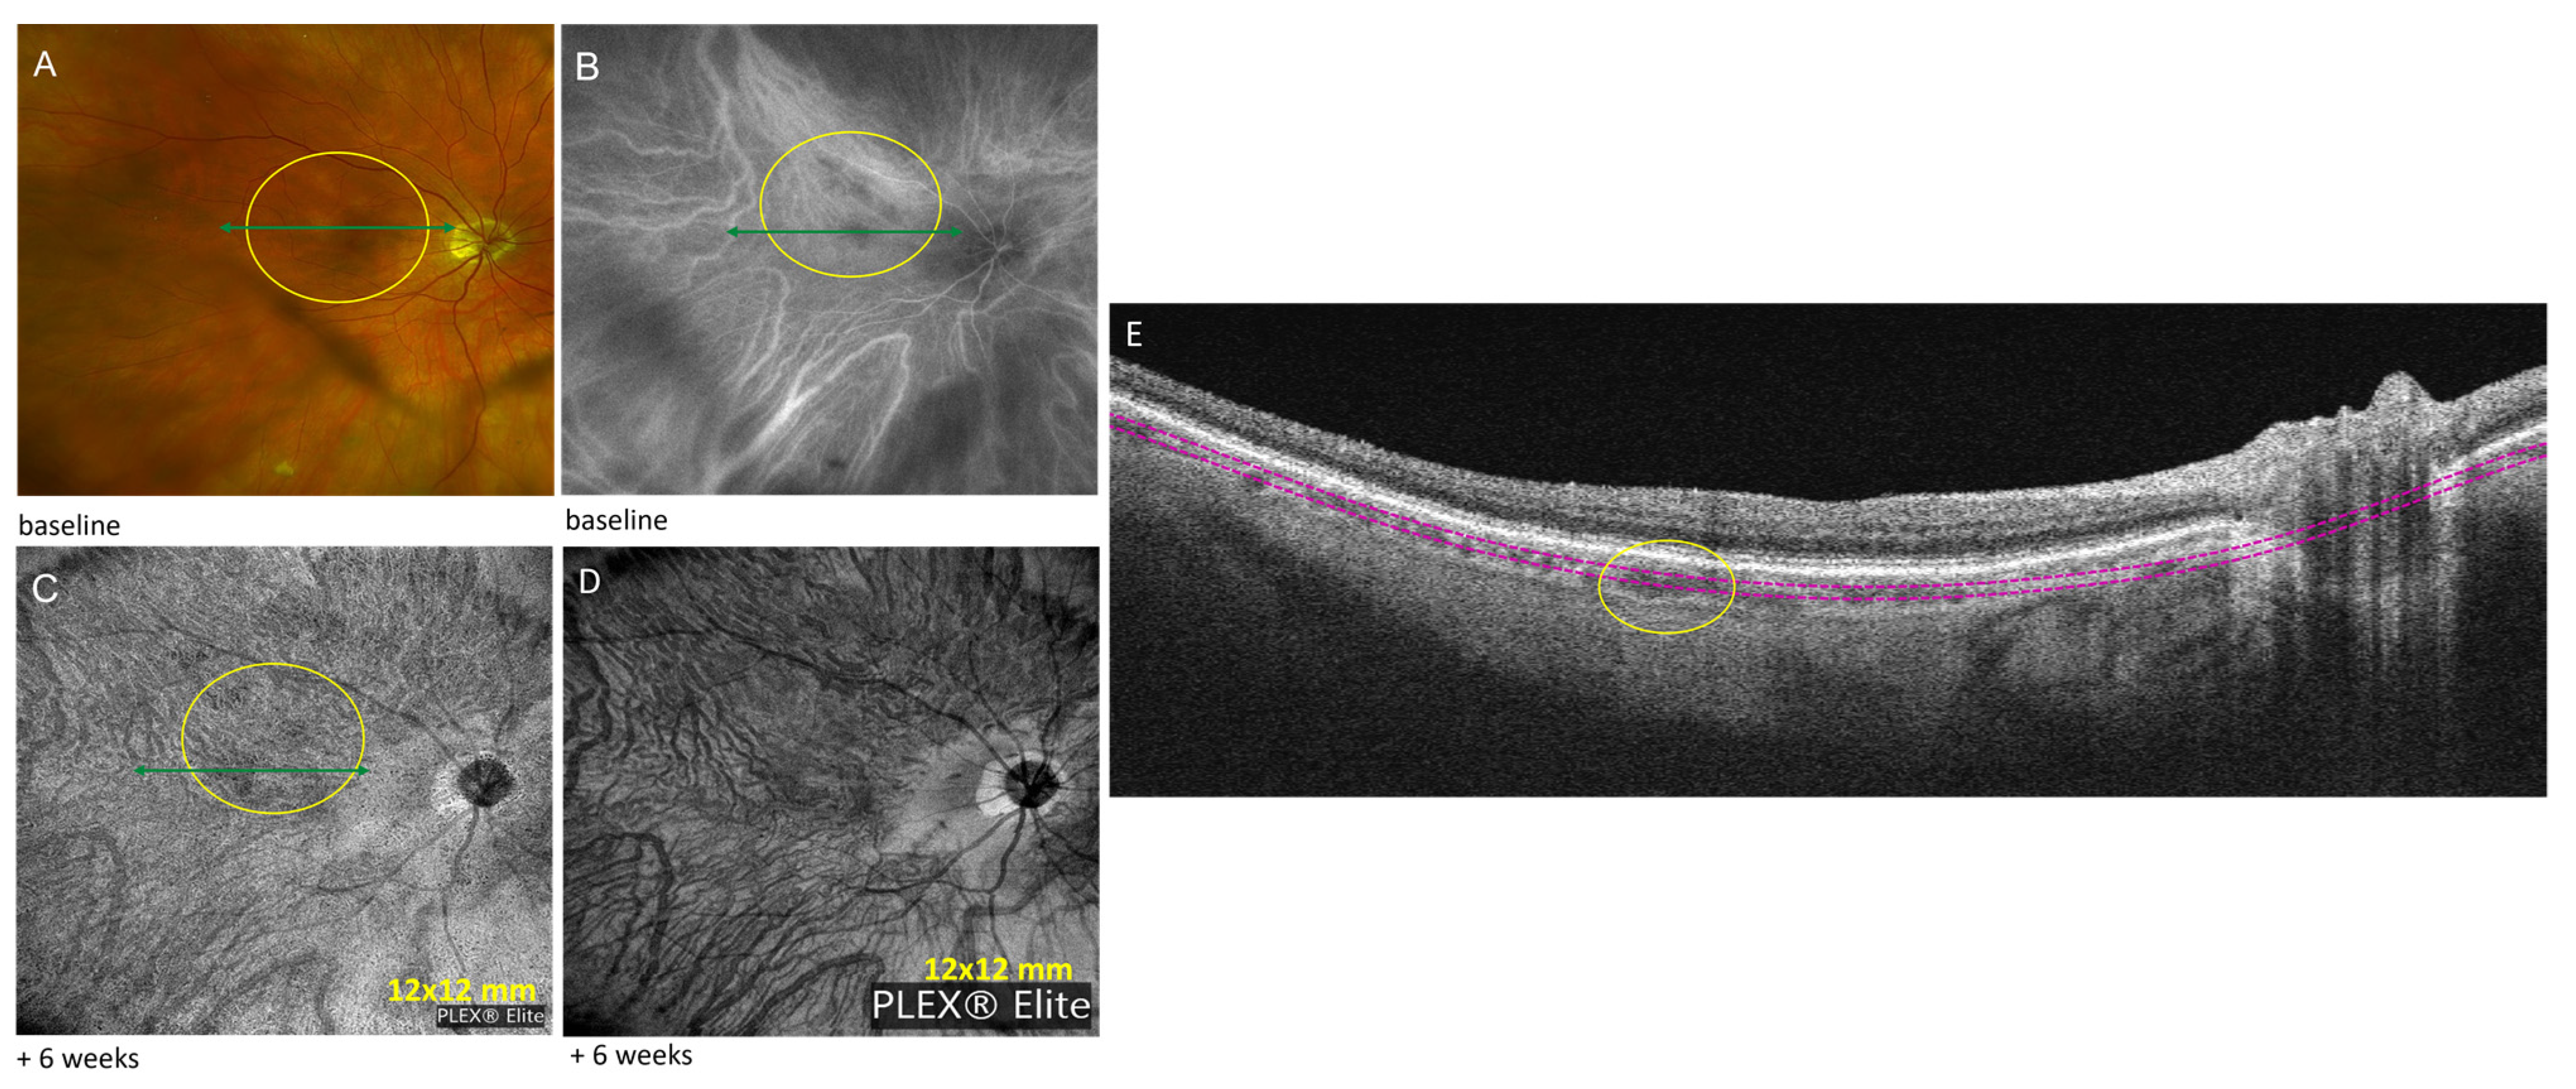

| 2 | Sarcoid choroidal granulomas | Hyper-reflective choroidal material: choroidal granulomas without subretinal or intraretinal fluid | Zeiss PLEX® Elite 9000 OCTA (12 mm × 12 mm): non-detectable flow signal in corresponding choroid; One month post-injection: size decrease Eleven months post-injection: no changes | Baseline: 220 | ||

| 2 | 74 F | Sarcoid choroidal granulomas | mono | Subtenon triamcinolone injection; adalimumab 40 mg subQ every two weeks | 20/20 | Hydroxyquinoline 200 mg daily |

| Intraocular immunomodulatory therapy discontinued | ||||||